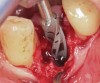

Prior to drilling the osteotomy, a landmark point on the patient scan was verified against direct visualization by placing the drill tip on the chosen anatomical landmark. Surgery proceeded under RADS guidance, in the form of auditory feedback (ie, mode-change and warning beeps) and haptic feedback (ie, resistance to drill motion) as well as visual guidance via a monitor (ie, navigation). To initiate the osteotomy, a 2.3-mm round drill was placed in the robotic guidance arm. As per the implant manufacturer's recommendations, three subsequent drills were used to perform the osteotomy in the prescribed location and angulation (Figure 4 and Figure 5). Implant placement was also achieved with the RADS system (Figure 6 and Figure 7).

Fig 6. Implant placement into the extraction socket under robotic guidance.

Figure 6